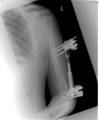

Post Op

Monolateral fixator applied using MIS technique with closed reduction